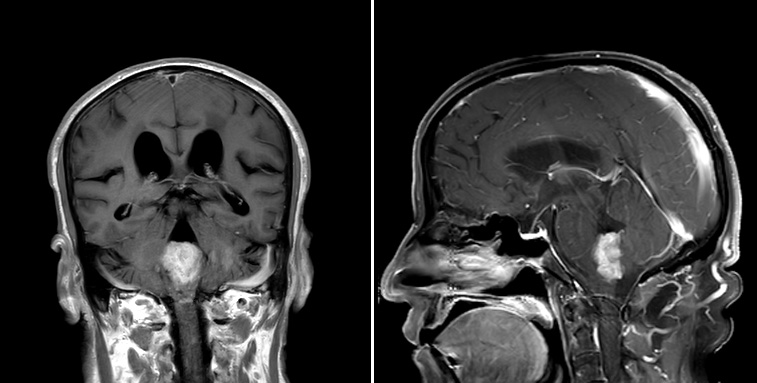

Radiology description

- Commonly discrete, well circumscribed mass with avid uniform contrast enhancement

- Hyperdense on computed tomography and T2 hyperintense on magnetic resonance imaging

- Reference: Childs Nerv Syst 2009;25:1203

Radiology images